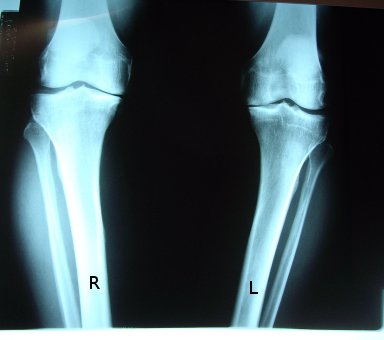

2006_x-ray

2009_Aug_x-ray

2009_pre-op_x-ray